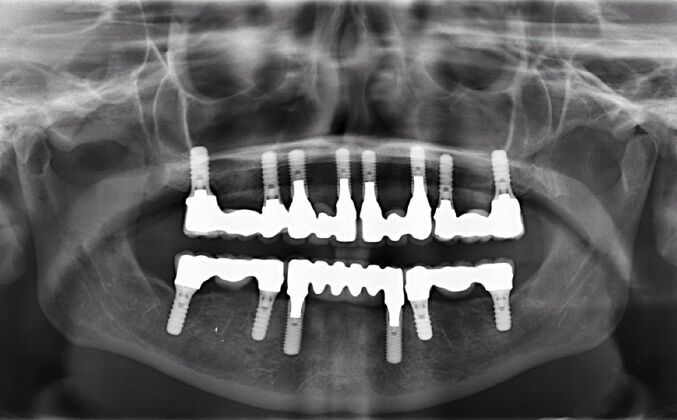

All-on-4/ Full Mouth Dental Implants / Teeth in a Day: Case 15- Full mouth implants-upper and lower

This medical professional was busy taking care of her patients all her life and had become frustrated with her recurrent cavities underneath her restorations after spending thousands of dollars on fillings, crowns, root canals and bridges. Patient found Dr Bidra online through a google search and sought care for full mouth implants (top and bottom). After extractions of all teeth, Dr Bidra designed her treatment such that there would be separate small segmented bridges as the patient had good bone underneath all her failing teeth

Procedures : extractions, implants, full mouth implants, full mouth reconstruction with implants